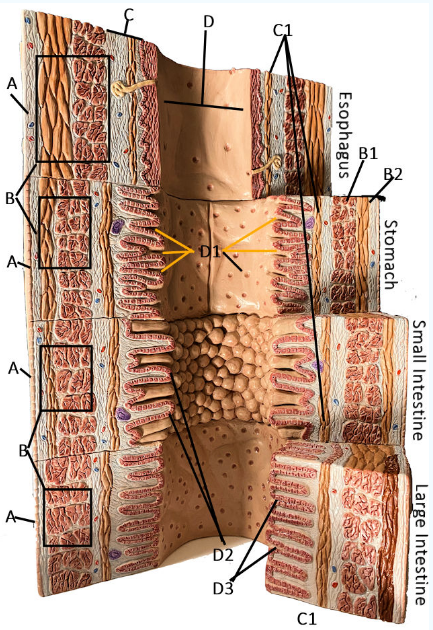

A

Serosa

B Esophagus

Muscularis externa: skeletal, skeletal/smooth, and smooth, circular and longitudinal

B Stomach

Oblique, circular, and longitudinal smooth muscle

B Small intestine

circular and longitudinal smooth muscle

B large intestine

circular and longitudinal smooth muscle

C

Submucosa: areolar and dense connective tissue

D

Lumen

D1

Gastric glands/pits

D2

Villi of small intestine

D3

Intestinal crypts of large intestine